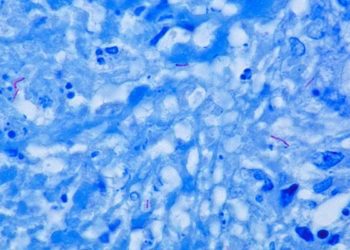

Chemotherapy-induced bone marrow nerve injury impairs hematopoietic regeneration

The relationship between hematopoietic regeneration and neuronal innervation is poorly understood, however it is known that many chemotherapeutic agents like cisplatin can cause sensory neuropathy. Using mouse models, researchers show that loss of adrenergic innervation of the bone marrow alters hematopoietic regeneration after insult and neuroprotective factors can enhance bone marrow recovery after injury.